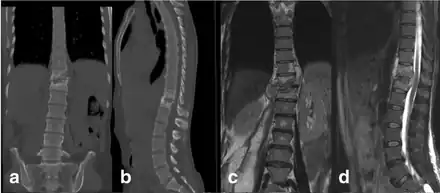

In the early stages of Pott's Disease, imaging techniques such as CT scans, MRIs, or plain radiographs are ordered. For a radiolucent lesion to appear on a plain X-ray, there must be a 30 percent loss of bone mineral, making it difficult to diagnose the early stages of Pott's Disease with a plain radiograph. CT is often used as a guide for biopsy. Overall, it is widely documented that MRI is superior to plain radiographs in diagnosing Pott's Disease. [2][4][1]